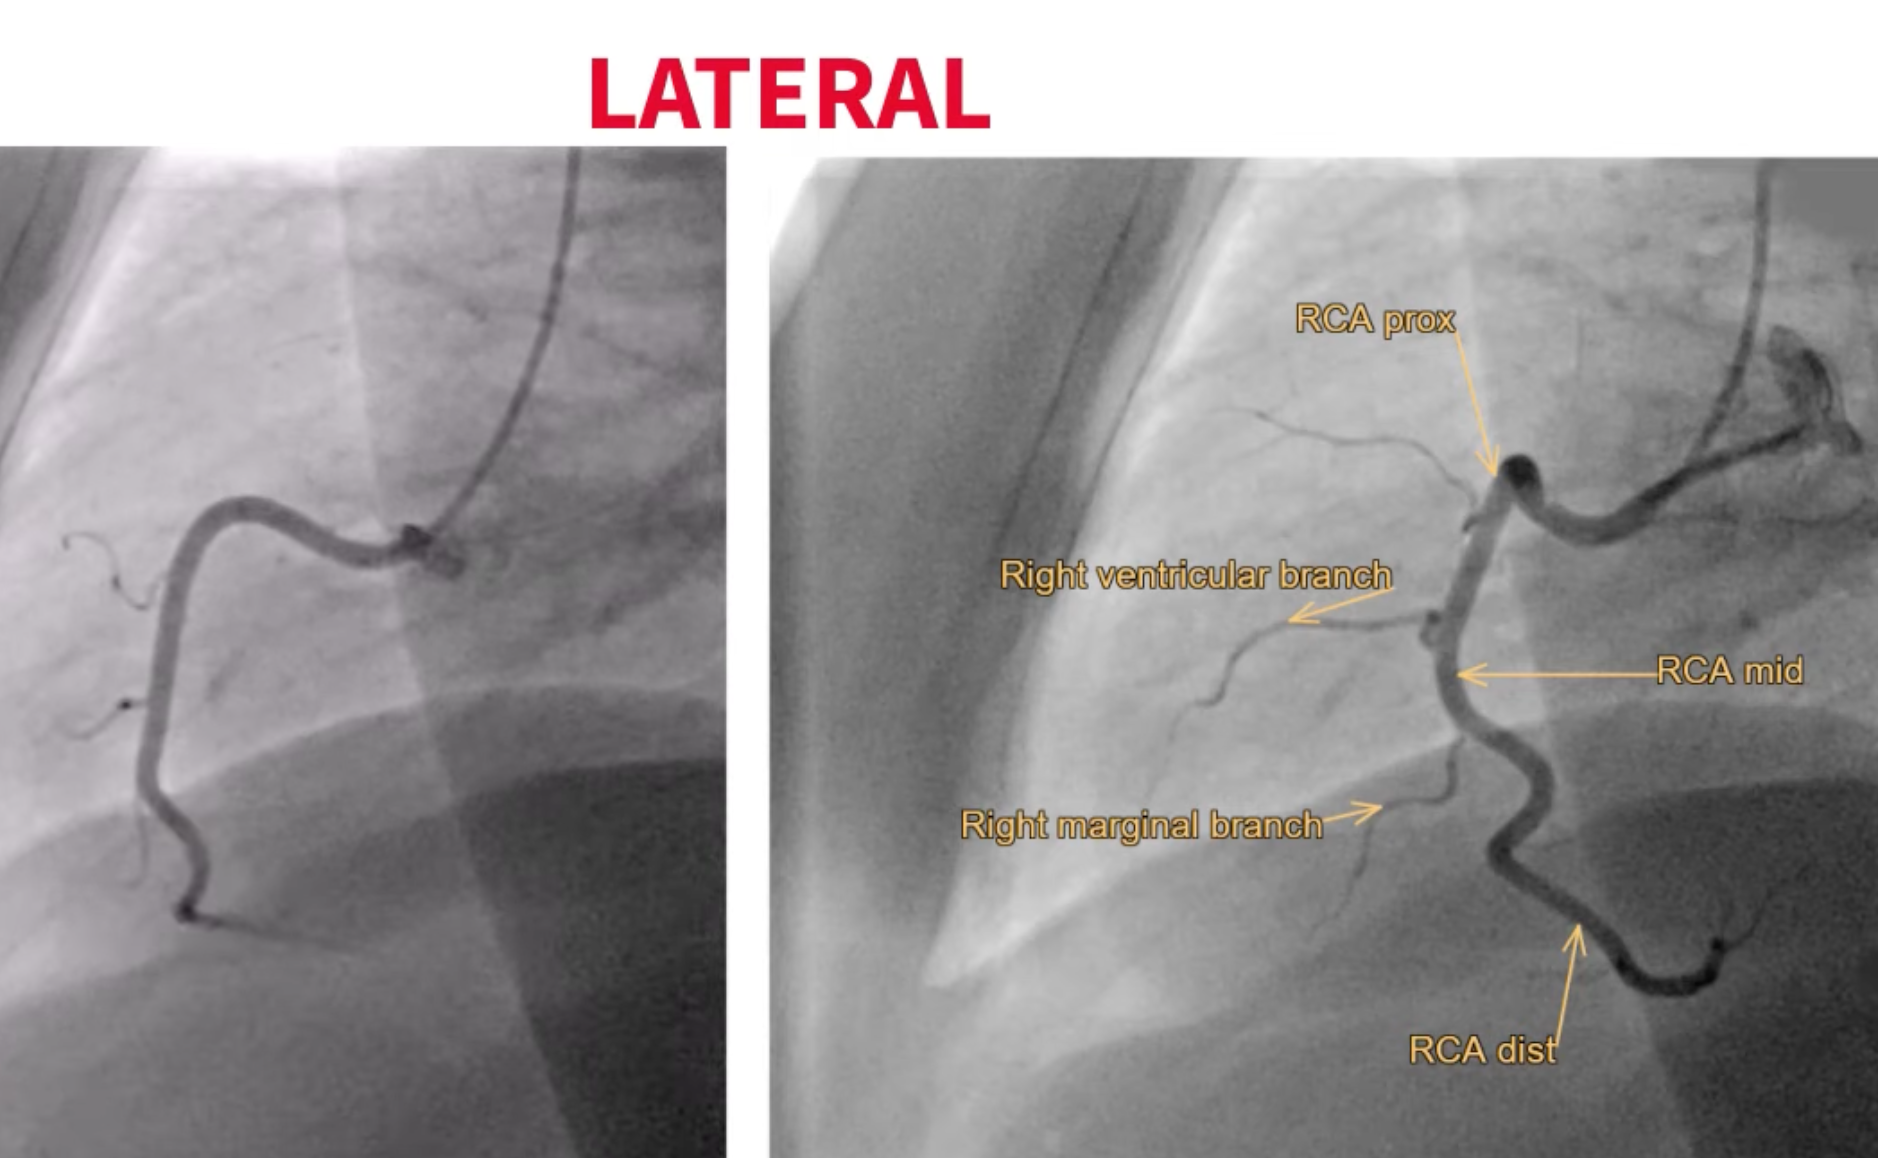

Lateral

- Engaging the right main: